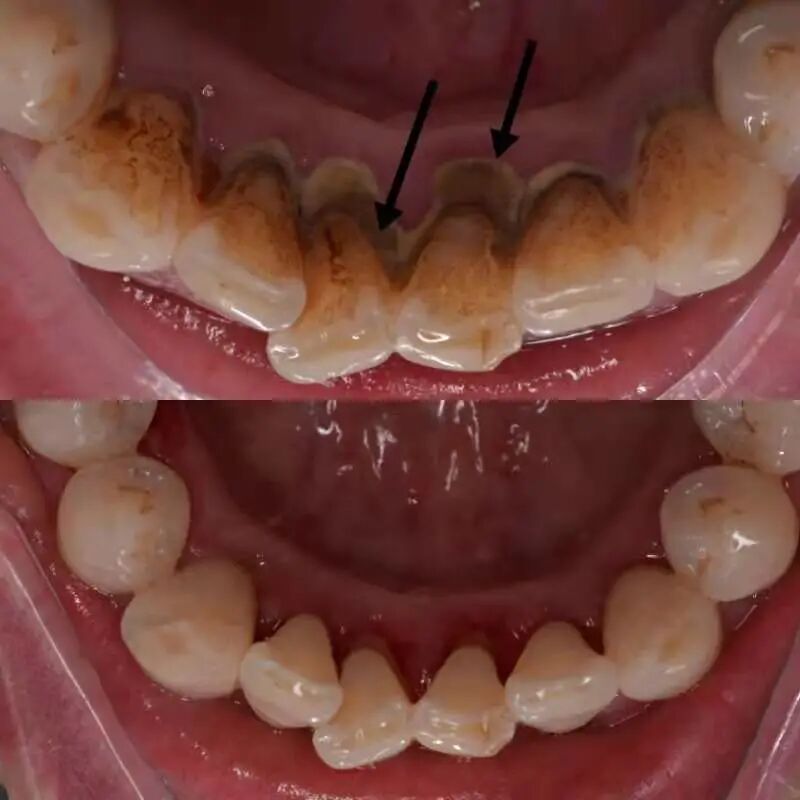

洗牙过程中有可能会出血

如果牙龈炎症较重、红肿

洗牙时可能会有明显的出血

但洗牙后很快就会缓解

不需要过分担心

(牙结石导致牙龈炎症较重,洗完牙后出血明显。作者供图)